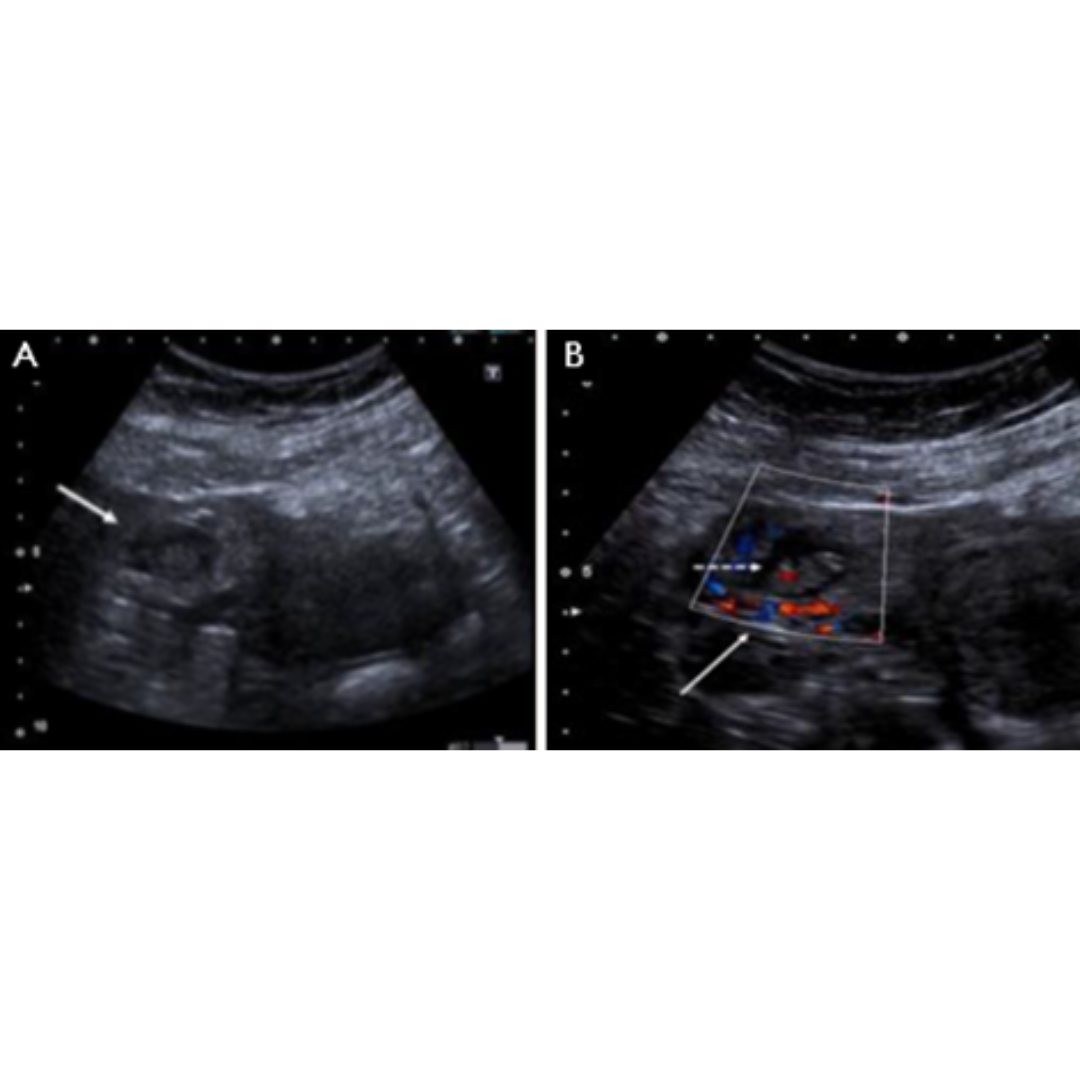

Apendicitis Aguda

Inflamación del apéndice cecal producida por obstrucción de su lumen, ya sea por fecalitos, tejido linfoide hiperplásico, parásitos o tumores.

Presenta varios estadios evolutivos: congestiva, flegmonosa, necrótica y perforada.

Signos US: aumento del diámetro del apéndice cecal (> 6 mm) y pared apendicular engrosada (> 3 mm), signo del fondo de saco ciego, apéndice no compresible, grasa peri apendicular hiperecogénica, la señal al Doppler color dependerá del estadio evolutivo (en fase aguda existirá hiperemia), puede existir apendicolito asociado.

Figura 1: Apéndice cecal aumentado de tamaño, con hiperemia y grasa periapendicular hiperecogénica. En B y C se observa el signo del fondo de saco ciego característico de afectación apendicular.